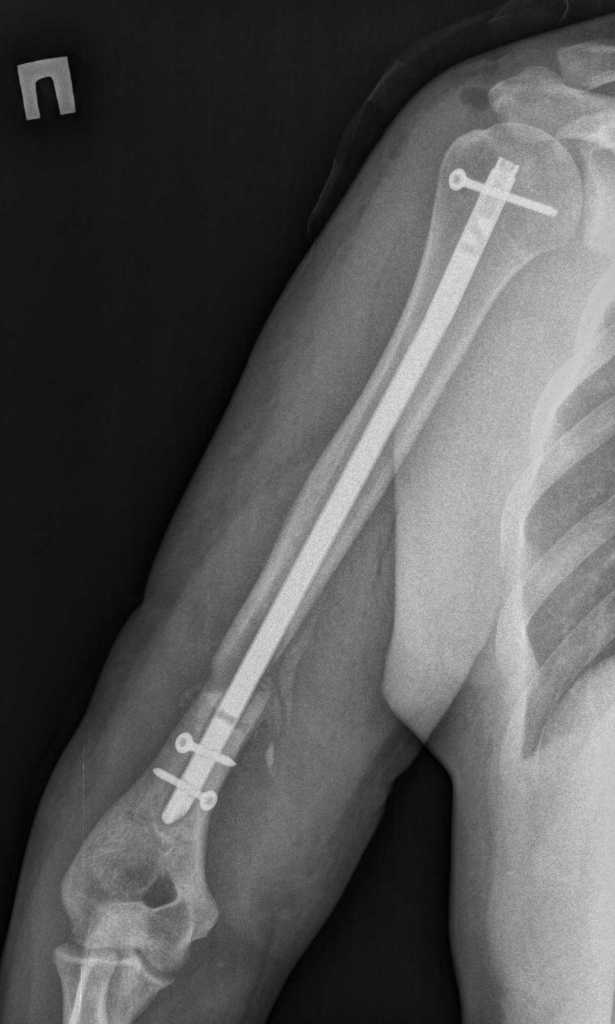

Re: Перелом штифта

Ретроградный БИОС обречен на неудачу в данном случае - слишком короткий дистальный фрагмент.

Здравствуйте. Открыто удалили дистальный фрагмент. После рассверливания заштифтовали более массивным штифтом. Спасибо за участие в обсуждении случая.

И он опять должен сломаться по проксимальному отверстию (Биомеханика вещь не меняющаяся)

Снимки "до" и "после" очень похожи, ...пациент молодой, повторный перелом конструкции скорее всего - вопрос времени. Проследить бы пациента дальше, как будет "срастаться".